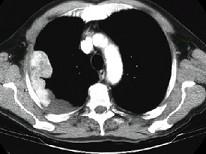

问题 男,53岁,胸痛1月余加重2周,CT检查,最可能的诊断为 ( )

选项 A.右侧石棉肺胸膜斑 B.右侧良性胸膜间皮瘤 C.右侧恶性胸膜间皮瘤 D.右侧胸膜转移瘤 E.右侧胸膜弥漫增厚

答案 C